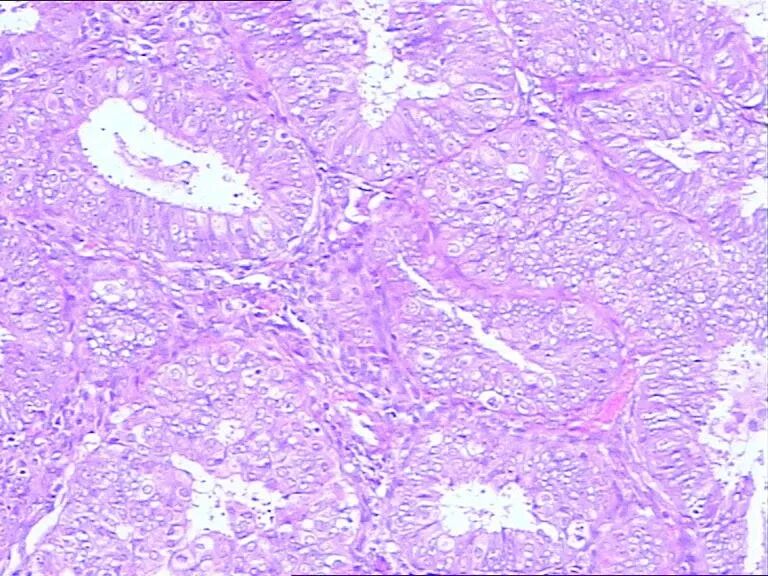

山东省德州市中医院 | 徐连泉 患者家属投诉我 我却成了他的“朋友” 由于种种原因,近年来,医患关系越发紧张。患者或其家属动辄就将医生投诉,病理医生也未能幸免。 而我,却因为患者家属的一次投诉,竟成了对方的“朋友”。 三年前,38岁的患者王某因不规则阴道流血3个月来我院妇科就诊。彩超显示其宫腔内膜增厚,遂刮宫送检。 切片出来后,我在显微镜下仔细观察分析,发现大部分腺体显著密集,大小不等,个别呈筛状,上皮细胞大多失去极性,轻-中度异型,可见核仁及核分裂像,间质稀少,部分消失。最后签发病理报告: (宫腔)高分化子宫内膜样腺癌 报告发出后,妇科医生便着手给王某准备手术,而王某的家属却非要先借片去省级医院会诊。 这当然无可厚非,我也同意。但在办理借片手续时,我按有关规定请借片人也就是王某的丈夫交纳100元的押金,等还切片时凭押金收条退回押金。 但是,他拒绝了!他认为片子本来就是用他媳妇身上的肉做出来的,凭啥不能给他,还非要交押金才能借片子? 我很无奈,说:这是国家及省里的有关文件规定的。并找出相关的文件给他看。然而,他根本不看,只说交押金还必须还片子就是不行,否则就投诉我。 果然,不一会儿,我就接到了医院医务科的电话,说有人把我投诉到了市长热线12345,让我去医务科给予答复。无奈,我只得赶紧带着国家卫生计生委及原山东省卫生厅(山东省卫生计生委)发布的相关文件去找医务科长。 国家卫生计生委和国家中医药管理局联合发布的《医疗机构病历管理规定(2013年版)》以及原山东省卫生厅发布的《山东省临床病理诊断与技术操作规程(试行)》中规定: 既然是“借,”就必须有“还”。如何保证病人及时归还切片?通常就是让借片者交纳一定数额的押金,并留下借片者的身份信息及联系电话。借片者非患者本人时,其须同时出示患者的身份信息,并一起留下。 看到国家及省里的相关文件,医务科长也只能按相关文件办事,如实回复12345。12345让患者家属遵从相关文件的规定。 最终他交纳押金,借走切片。 第二天,省里的会诊报告出来了,是:(宫腔)子宫内膜非典型增生,建议一月后复查。 一月后,患者的阴道仍然流血,她就直接去了上次会诊的那家省级医院。在那里,她再刮宫送检,病理诊断为子宫内膜样腺癌。 患者当即就入院做了手术,术后病理检查发现,宫腔内的癌组织已侵及子宫肌层。 还切片时,患者的丈夫再无原先的满脸怒气,不仅为他早先的行为表示道歉,还非要请我吃饭,要和我交“朋友”。 在我的询问下,他将媳妇去省里会诊、在家等待、去省里复诊、再刮宫送检以及手术治疗的整个过程详细的讲与我听。说是早信我的诊断早手术就好了。 当然,作为一名医生。治病救人是我的职责,饭,自然是不会去吃的。 此后,他还真就把我当成了“朋友”,每当他及他的家人甚至他的亲戚、朋友身体出现了什么病症,首先想到的就是向我咨询。 需要门诊或住院治疗的,全都首先来我们医院。我也的确感到了“麻烦”,但这样的“麻烦”却也让我内心感到一丝的欣慰: 还有什么能比患者对自己的信任更高兴呢! 文字由徐连泉原创,部分图片来源于网络,版权归病理大师所有。